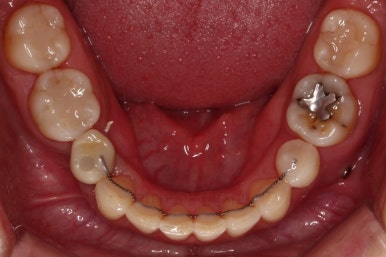

초진 시 입안의 모습인데요.

왜 그런지 비밀이 풀리는 것 같죠?

윗니는 한 쪽이 치아 2개가 결손이면서 유치가 하나 남아있고요.

아랫니는 한 쪽은 1개, 반대편은 2개 치아가 결손이었습니다.

도합 5개의 치아가 결손이었는데요.

결손 위치의 갯수가 위아래 좌우 다 달라서 중앙선이 맞을래야 맞을 수가 없는 상황이었죠.

결손치아 주위 치아들은 쓰러지고 비틀어져 있어서 장기적으로 좋지 못한 상황이었고요.

좀 더 디테일하게 윗니 작은 앞니 1개가 왜소치아라서 치아 크기도 맞지 않은 상황이었습니다.